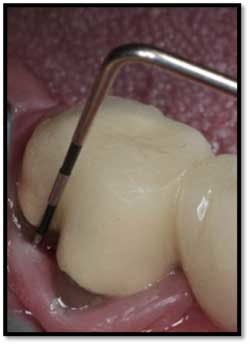

#18 buccal reflected in a mirror. Now probes 2mm reduced from 9mm

LL Quadrant#27M, now 2mm reduced from 6mm, tissue tight and firm

#26 F now 2mm. All tissue is light pink, tight and firm.